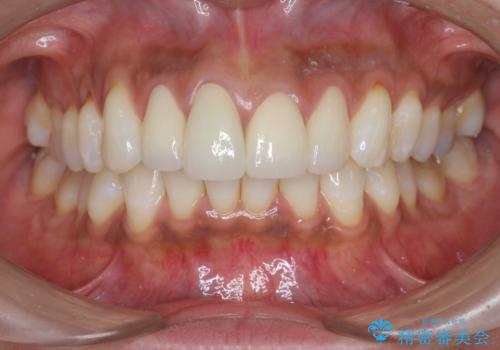

金属色の見える前歯 オールセラミックで審美治療

- 前歯のクラウンの見た目が不自然、歯の根元が見えたり金属色が気になるので改善したい、とセラミック治療を希望され来院されました。

歯肉の位置変化による審美障害を改善するため、オールセラミックジルコニアクラウンで再治療を行い審美性の改善を計画します。

- 52.8万円(ジルコニアクラウン×4・仮歯×4)費用は治療当時の料金となります

見た目が自然になり、色調も天然の歯とおなじような透明感のある色調が再現され、大変喜んでいただくことができました。